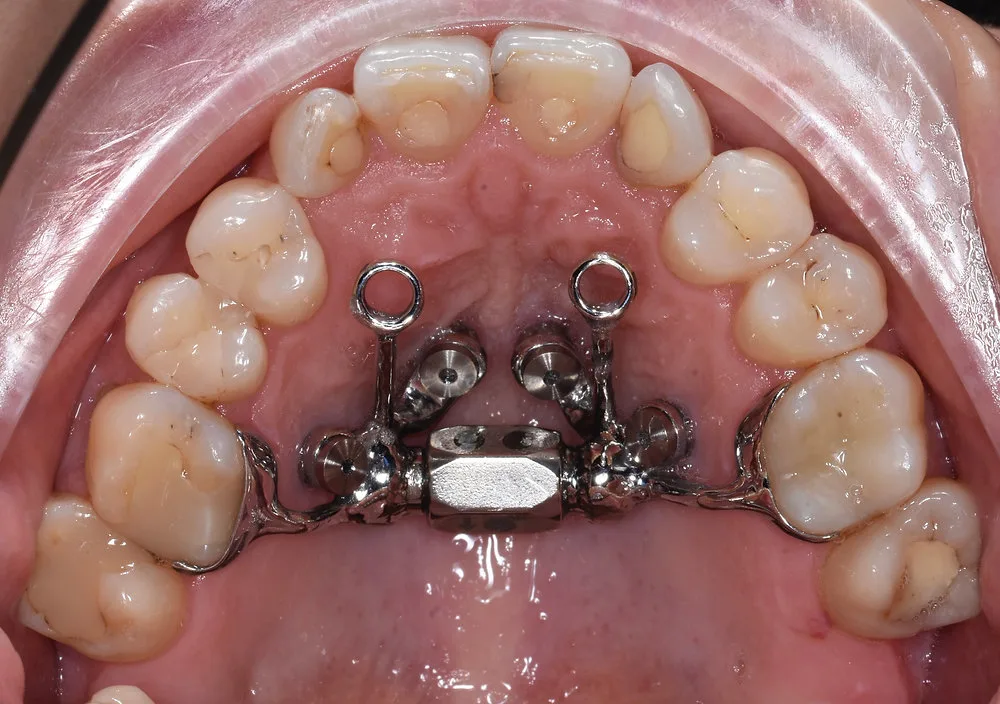

Zgryz krzyżowy szkieletowy u dzieci leczymy ekspanderem podniebienia (aparat Hassa lub ruchomy) lub aparatem funkcjonalnym. W oknie wzrostowym poszerzenie górnej szczęki jest możliwe bez operacji – to jedyna taka szansa.

Zgryz krzyżowy szkieletowy u dzieci w trakcie wzrostu leczymy najczęściej ekspanderem podniebienia – aparatem rozszerzającym górną szczękę. Może to być aparat stały (śruba podniebienna, aparat Hassa) lub ruchomy, zależnie od wieku i zakresu korekty. Ekspander działa na szew podniebienny pośrodkowy, który u rosnącego dziecka jest jeszcze elastyczny – rozszerza szczękę i eliminuje przyczynę wady. Po ekspanderze często konieczny jest aparat stały dla precyzyjnego ustawienia zębów. Wczesna interwencja (ok. 7–9 lat) daje najlepsze efekty.